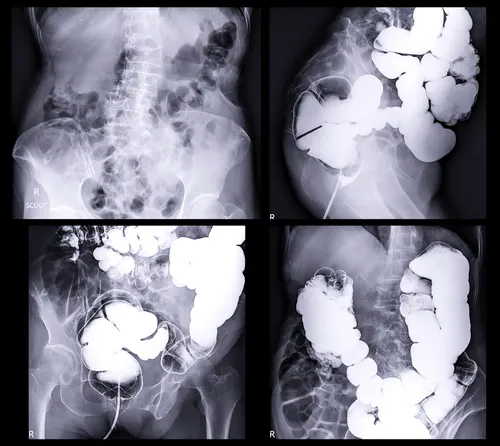

La prueba más efectiva sigue siendo la colonoscopía.“Es un estudio que se hace bajo anestesia. El doctor pone un tubo con una cámara pequeña y mira todo el intestino. Lo bueno es que también puede quitar pólipos y hacer biopsias”, explica.